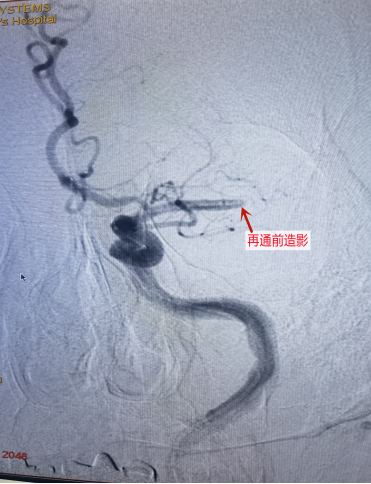

再通前造影

经神经内科医生仔细查体评估,考虑患者为急性颅内大动脉闭塞可能,但由于王大爷为“醒后卒中”,发病至少12小时,因此错过了最佳的血管再通治疗时间,此时他的情况十分危急……

经过科室介入团队与家属充分的沟通后,决定为患者急诊进行头颈部血管和脑组织灌注评估(CTA+CTP),进一步了解患者是否存在可挽救的缺血脑组织(俗称“缺血半暗带”)。

庆幸的是,缺血区域还有较大可挽救的脑组织,如立即“再通”,王大爷还有机会获得较好临床预后。

而王大爷的病情就是因为左侧大脑的主要动脉(称“大脑中动脉”)发生了急性闭塞,导致失语及右侧肢体出现完全性瘫痪等。